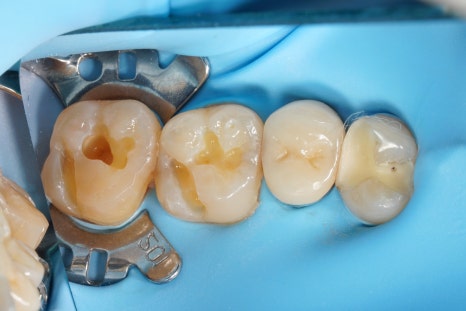

접착 치의학에 기반한

최소침습 치의학,

<레진 빌드업>으로

당일에 끝낼 수도 있습니다.

그리고 이렇게 하기 위해서는

러버댐이라는 재료를 잘 써야 해요.